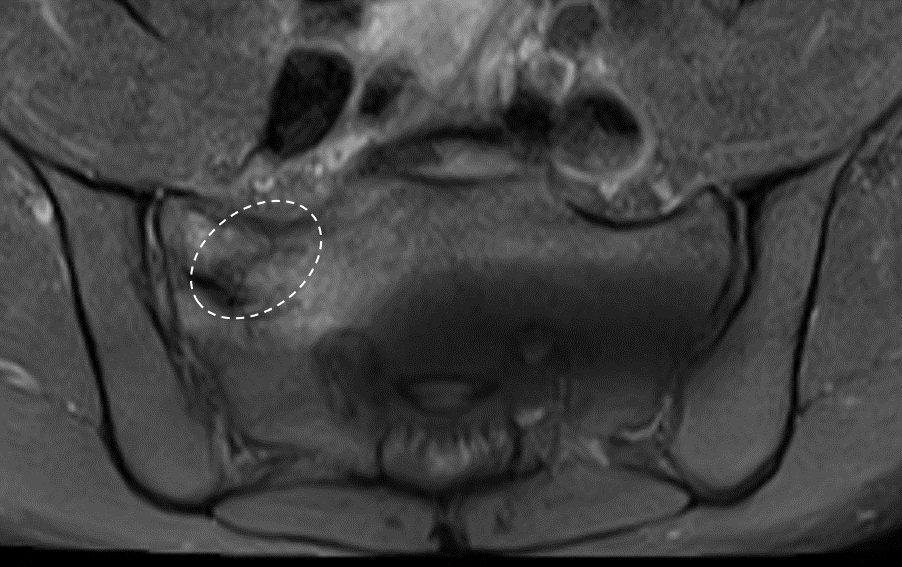

Fluoroscopy-guided imaging demonstrated the precise delivery of the patient’s own bone marrow concentrate into the deteriorating bone surrounding the symphysis pubis and into the degenerated joint itself. This approach designed to support healing, may help reduce inflammation, and may help promote stability in the affected area.

The images below, taken several months after the orthobiologic procedure, demonstrate significant improvement in the condition of the symphysis pubis joint.

The follow-up images indicate a restored joint space in the symphysis pubis, with improvements in the surrounding bone structure. The patient reported noticeable improvement, noting that 80–90% of his symptoms had diminished and that he experiences minimal daily discomfort. This outcome illustrates the potential role of orthobiologic procedures in supporting joint health and function.